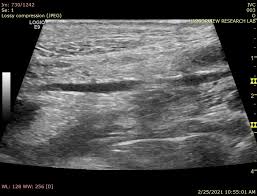

복부 초음파 검사 절차

검사는 대체로 10~20분 내외로 끝나는 간단한 과정입니다.

- 젤 도포: 초음파 탐촉자와 피부 접촉 향상을 위해 복부에 젤을 바름

- 탐색: 탐촉자를 위·아래·양옆으로 이동하며 각 장기를 촬영

- 체위 변화: 장기 위치에 따라 옆으로 눕거나 숨을 들이쉬게 요청